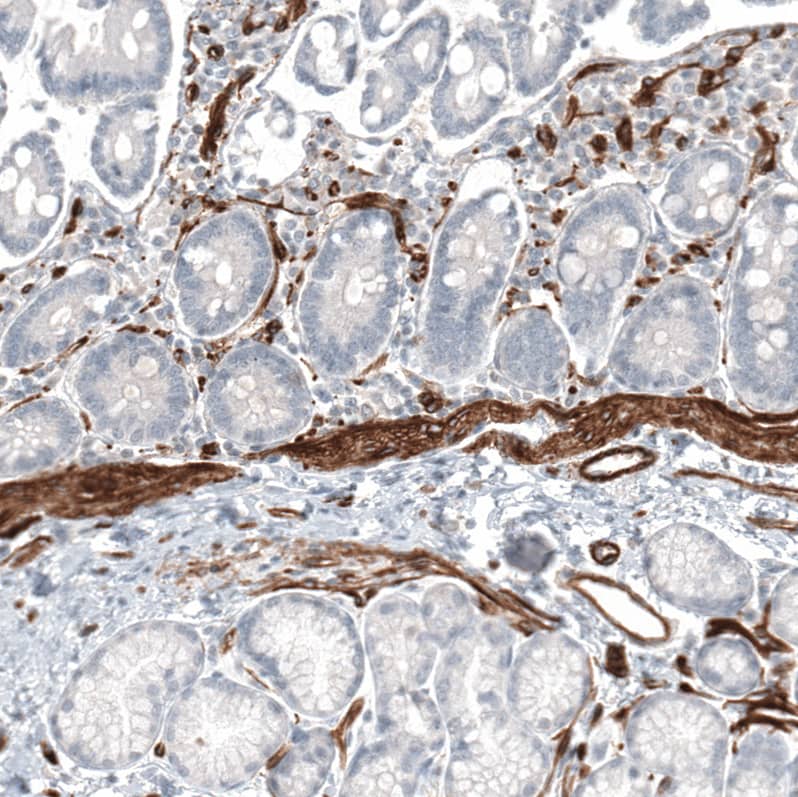

Staining of human duodenum shows strong cytoplasmic positivity in smooth muscle cells.